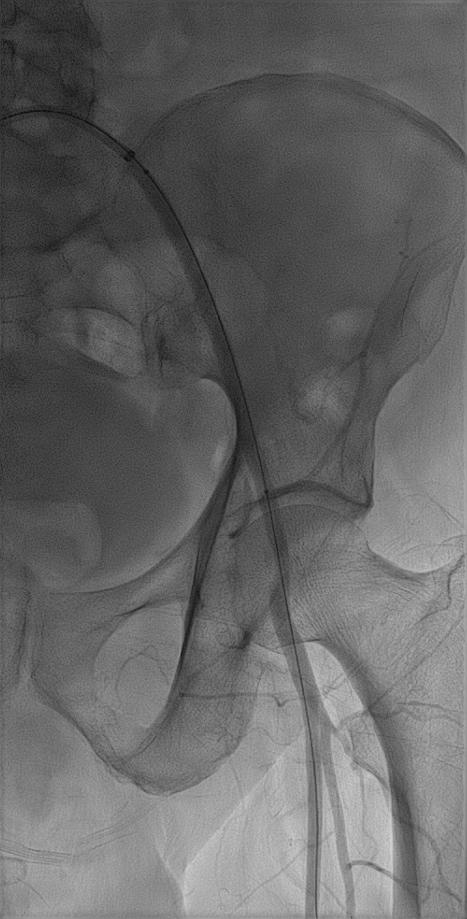

术前详解

(1)髂总动脉开口处病变,需要支架能够精准定位,既不能覆盖腹主动脉分叉型处遮挡对侧血流,又不能向髂总动脉内移牺牲有效锚定区。

(2)病变全长约115mm,预计覆盖血管全长约135mm。LCA=7.4mm,LEIA=5.7mm,要实现6mm到8mm的直径渐变。

(3)LIIA起始部重度狭窄,RIIA完好,双侧股深动脉,股浅动脉均正常。

影像1:术前测量及三维影像